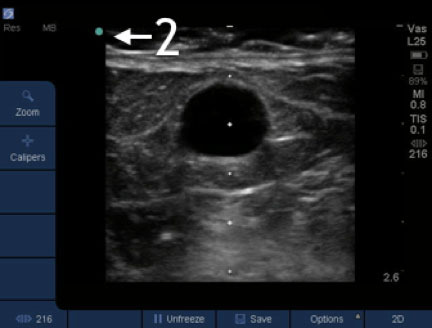

Dialysis Using the Transducer Image

2. Marker